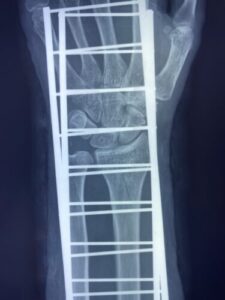

【橈骨遠位端骨折】コーレス骨折の治療とリハビリ|手術以外の選択肢と後遺症…